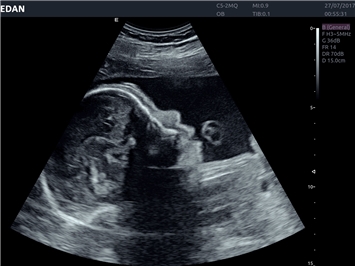

• 3D/4D-визуализация с автоматическим редактированием объема (eFace)

• Акушерства и гинекологии

• Педиатрии